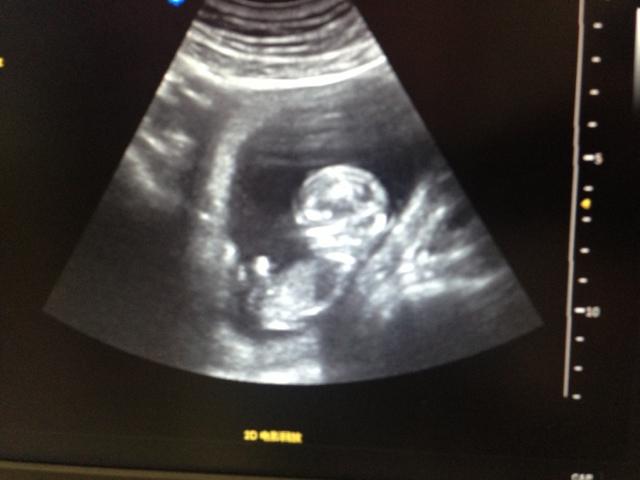

4.孕期按时产前检查,遵从正确的妊娠期指导,及时完善四维彩超及磁共振检查。